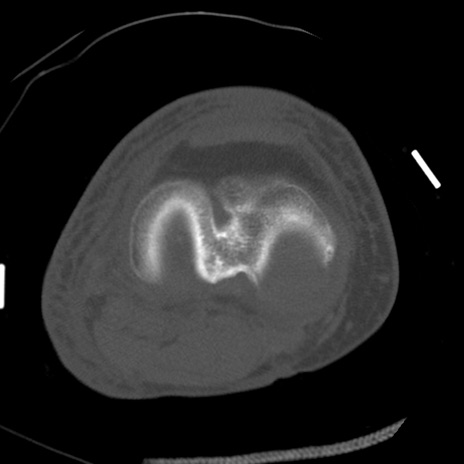

症例28 右膝関節CT(横断像)

右膝関節CT